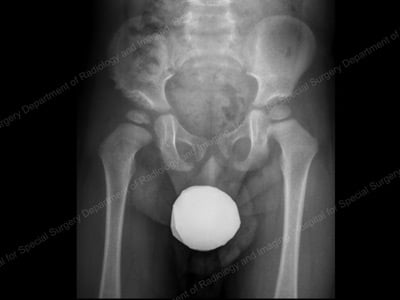

Anterior-to-posterior (front-to-back) preoperative X-ray of a dislocated right hip in toddler (shown at left).

In children, hip dysplasia more frequently affects the left hip than the right. About 80% of cases follow this pattern. The condition can, however, be present in both hips.